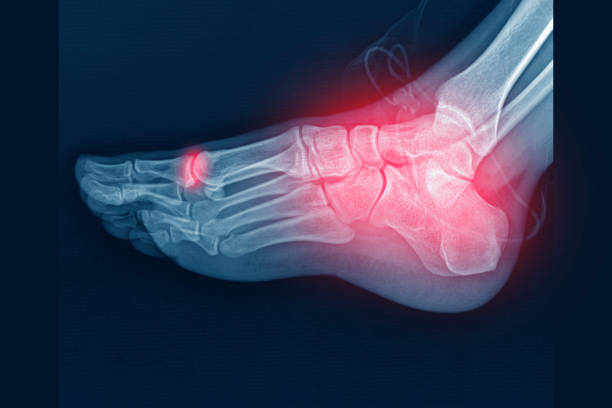

골다공증은 뼈 속에 있는 뼈가 점차적으로 없어지는 질병입니다. 이는 뼈가 흡수되어 뼈의 밀도가 감소하게 되어 발생합니다. 뼈의 밀도가 감소하면 뼈가 약해지고, 따라서 골절이 쉽게 발생할 수 있습니다. 골다공증은 주로 고령자에게서 발생하지만, 젊은 세대에서도 발병할 수 있습니다.

뼈 건강에 대한 오해와 잘못된 정보는 심각한 문제가 될 수 있습니다. 정상범위 오차로 T-score가 -2.5보다 살짝 위로 올라가는 경우라도, 골다공증의 위험이 존재할 수 있습니다. 따라서 뼈 건강을 관리하고 예방하기 위해서는 전문가의 조언을 듣고 치료 계획을 철저히 따라가는 것이 중요합니다.